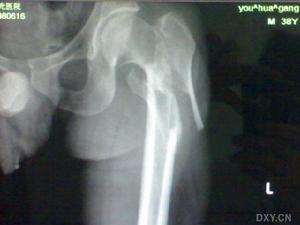

股骨粗隆部骨折 骨折內固定術股骨粗隆部骨折是常見、多發病,多見於老年人,其治療多趨向於內固定治療。PFNa是近年來為治療股骨粗隆部骨折而設計的髓內固定系統。2005年8月~2006年9月用PFNA內固定治療10例股骨粗隆部骨折患者,取得了良好的效果。

8例採用連續硬膜外麻醉,腰硬聯合麻醉1例,全麻1例。患者置於骨科牽引手術床上,牽引閉合復位,C型臂X線機透視復位成功後,取股骨大轉子上方3-5cm切口,用三稜錐自大轉子尖內側向股骨髓腔方向開口,透視見三稜錐進針點和方向好後插入導針,用彈性鑽擴大轉子入口,將安裝在瞄準器手柄上的主釘插入股骨近端髓腔內,深度合適後調整前傾角,通過瞄準器近端鎖孔向股骨頸內擰入導針1枚,正位透視導針位於股骨頸中下1/3,側位透視下導針位於股骨頸正中,空心鑽頭沿導針鑽孔,只鑽透外側皮質,沿導針方向打入螺鏇刀片,在定位器引導下打入遠端2枚鎖釘,取下定位器,因切口小,損傷小,一般不用放置引流管。術後處理術後使用抗生素1-3天,預防性使用抗凝劑1周,麻醉過後即可坐起,術後第2天行關節活動肌肉鍛鍊,可扶拐下地練習行走,根據骨折類型和復位情況決定傷肢不負重或部分負重。出院後每月複診1次X線片見骨痂生長良好,骨折線模糊即可判斷為骨折臨床癒合。

股骨粗隆間骨折股骨粗隆間骨折是股骨近端最常見的骨折之一,多發生於老年人,易伴有骨質疏鬆和內科疾病,雖多為低能量損傷所致,但若未及時有效地治療,及易留下髖內翻、肢體短縮等後遺症,加強對圍手術期處理,術前應對病人進行全面系統的檢查,發現並存症並予相應治療。

若長期臥床易發生肺部感染、泌尿系統感染、褥瘡等嚴重併發症。現多主張對有條件的患者儘早手術治療,以獲得穩定的復位,牢固的內固定,使患者早日恢復功能。

PFNa是一種新型內固定系統,其特點在於頭釘為直徑螺鏇刀片,通過外側切口自動完成抗鏇轉鎖定,只打開外側皮質,不移除骨質即便是在骨質疏鬆非常嚴重的患者,仍可以感覺到螺鏇刀片牢固的錨合力,螺鏇刀片可以很順暢地鏇轉,當打入螺鏇刀片時不會發生股骨頭和股骨頸分離及股骨頭和股骨頸鏇轉,主釘具有6度外偏角,方便從大粗隆頂部插入;遠端一鎖定孔即可選擇靜態或動態鎖定;儘可能長的尖端及凹槽設計,使PFNA插入方便並且避免了局部應力集中;對於長型PFNA,也可以二期動態化。

PFNA特點有:屬於髓內固定,即保持了AO堅強固定的理念,生物力學穩定堅強,可早期下地行走。又體現了BO和微創外科的精髓,手術切口僅3~5cm,手術時間短,平均60min,出血少,平均72.2ml,不需輸血。頭釘為直徑11㎜的螺鏇刀片,導針只需一枚,且頭頸部位無需用鑽開孔,主釘6度外偏角,從大粗隆頂部即可插入,簡化了手術操作,縮短手術時間,降低了透視次數。PFNA具有多種型號,適應於Evans分型的各型轉子間骨折、對於轉子下骨折及合併股骨幹中上段骨折患者可選擇加長型。

綜上所述,套用PFNA治療股骨轉子間骨折具有固定確實,創傷小,下床活動早,骨折癒合快,併發症少等優點,是治療股骨粗隆間骨折的理想器械。